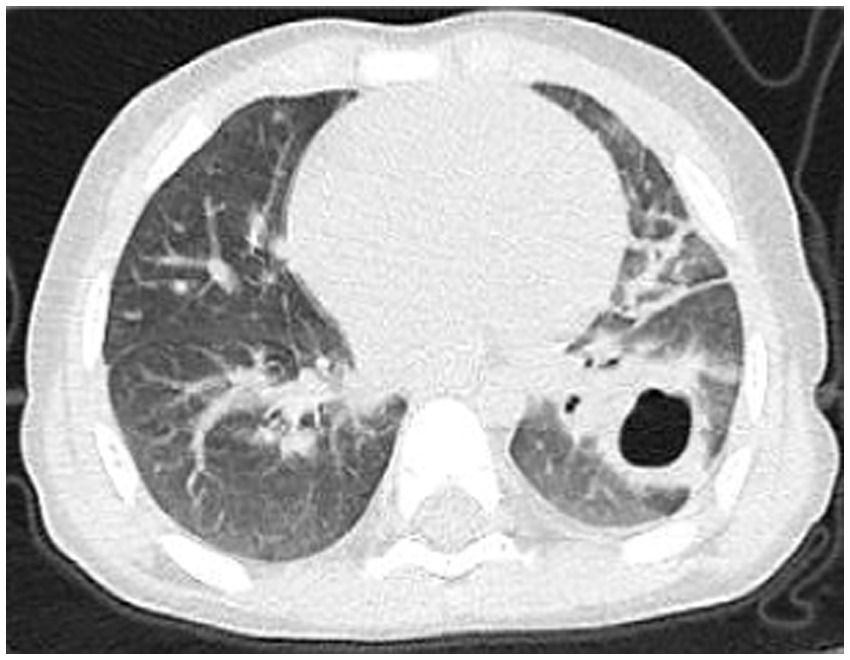

A 2-year-old male patient presented with a 7-day history of paroxysmal cough with sputum and rhinorrhea, followed by 4 days of fever (peak temperature 39.7 °C). No wheezing or shortness of breath was noted. Prior outpatient treatment with cefuroxime, azithromycin, and methylprednisolone sodium succinate yielded no improvement. Initial blood tests revealed white blood cell count (WBC) 3.7 × 10^9/L, lymphocytes (LY) 26%, neutrophils (NEUT) 67%, hemoglobin (HGB) 120 g/L, platelet count (PLT) 243 × 10^9/L, and C-reactive protein (CRP) 148.24 mg/L. Chest computed tomography (CT) (Figure 1) indicated pneumonia with lung consolidation, prompting hospital admission for severe pneumonia.

Figure 1

Chest CT scan on the 6th day of the illness.